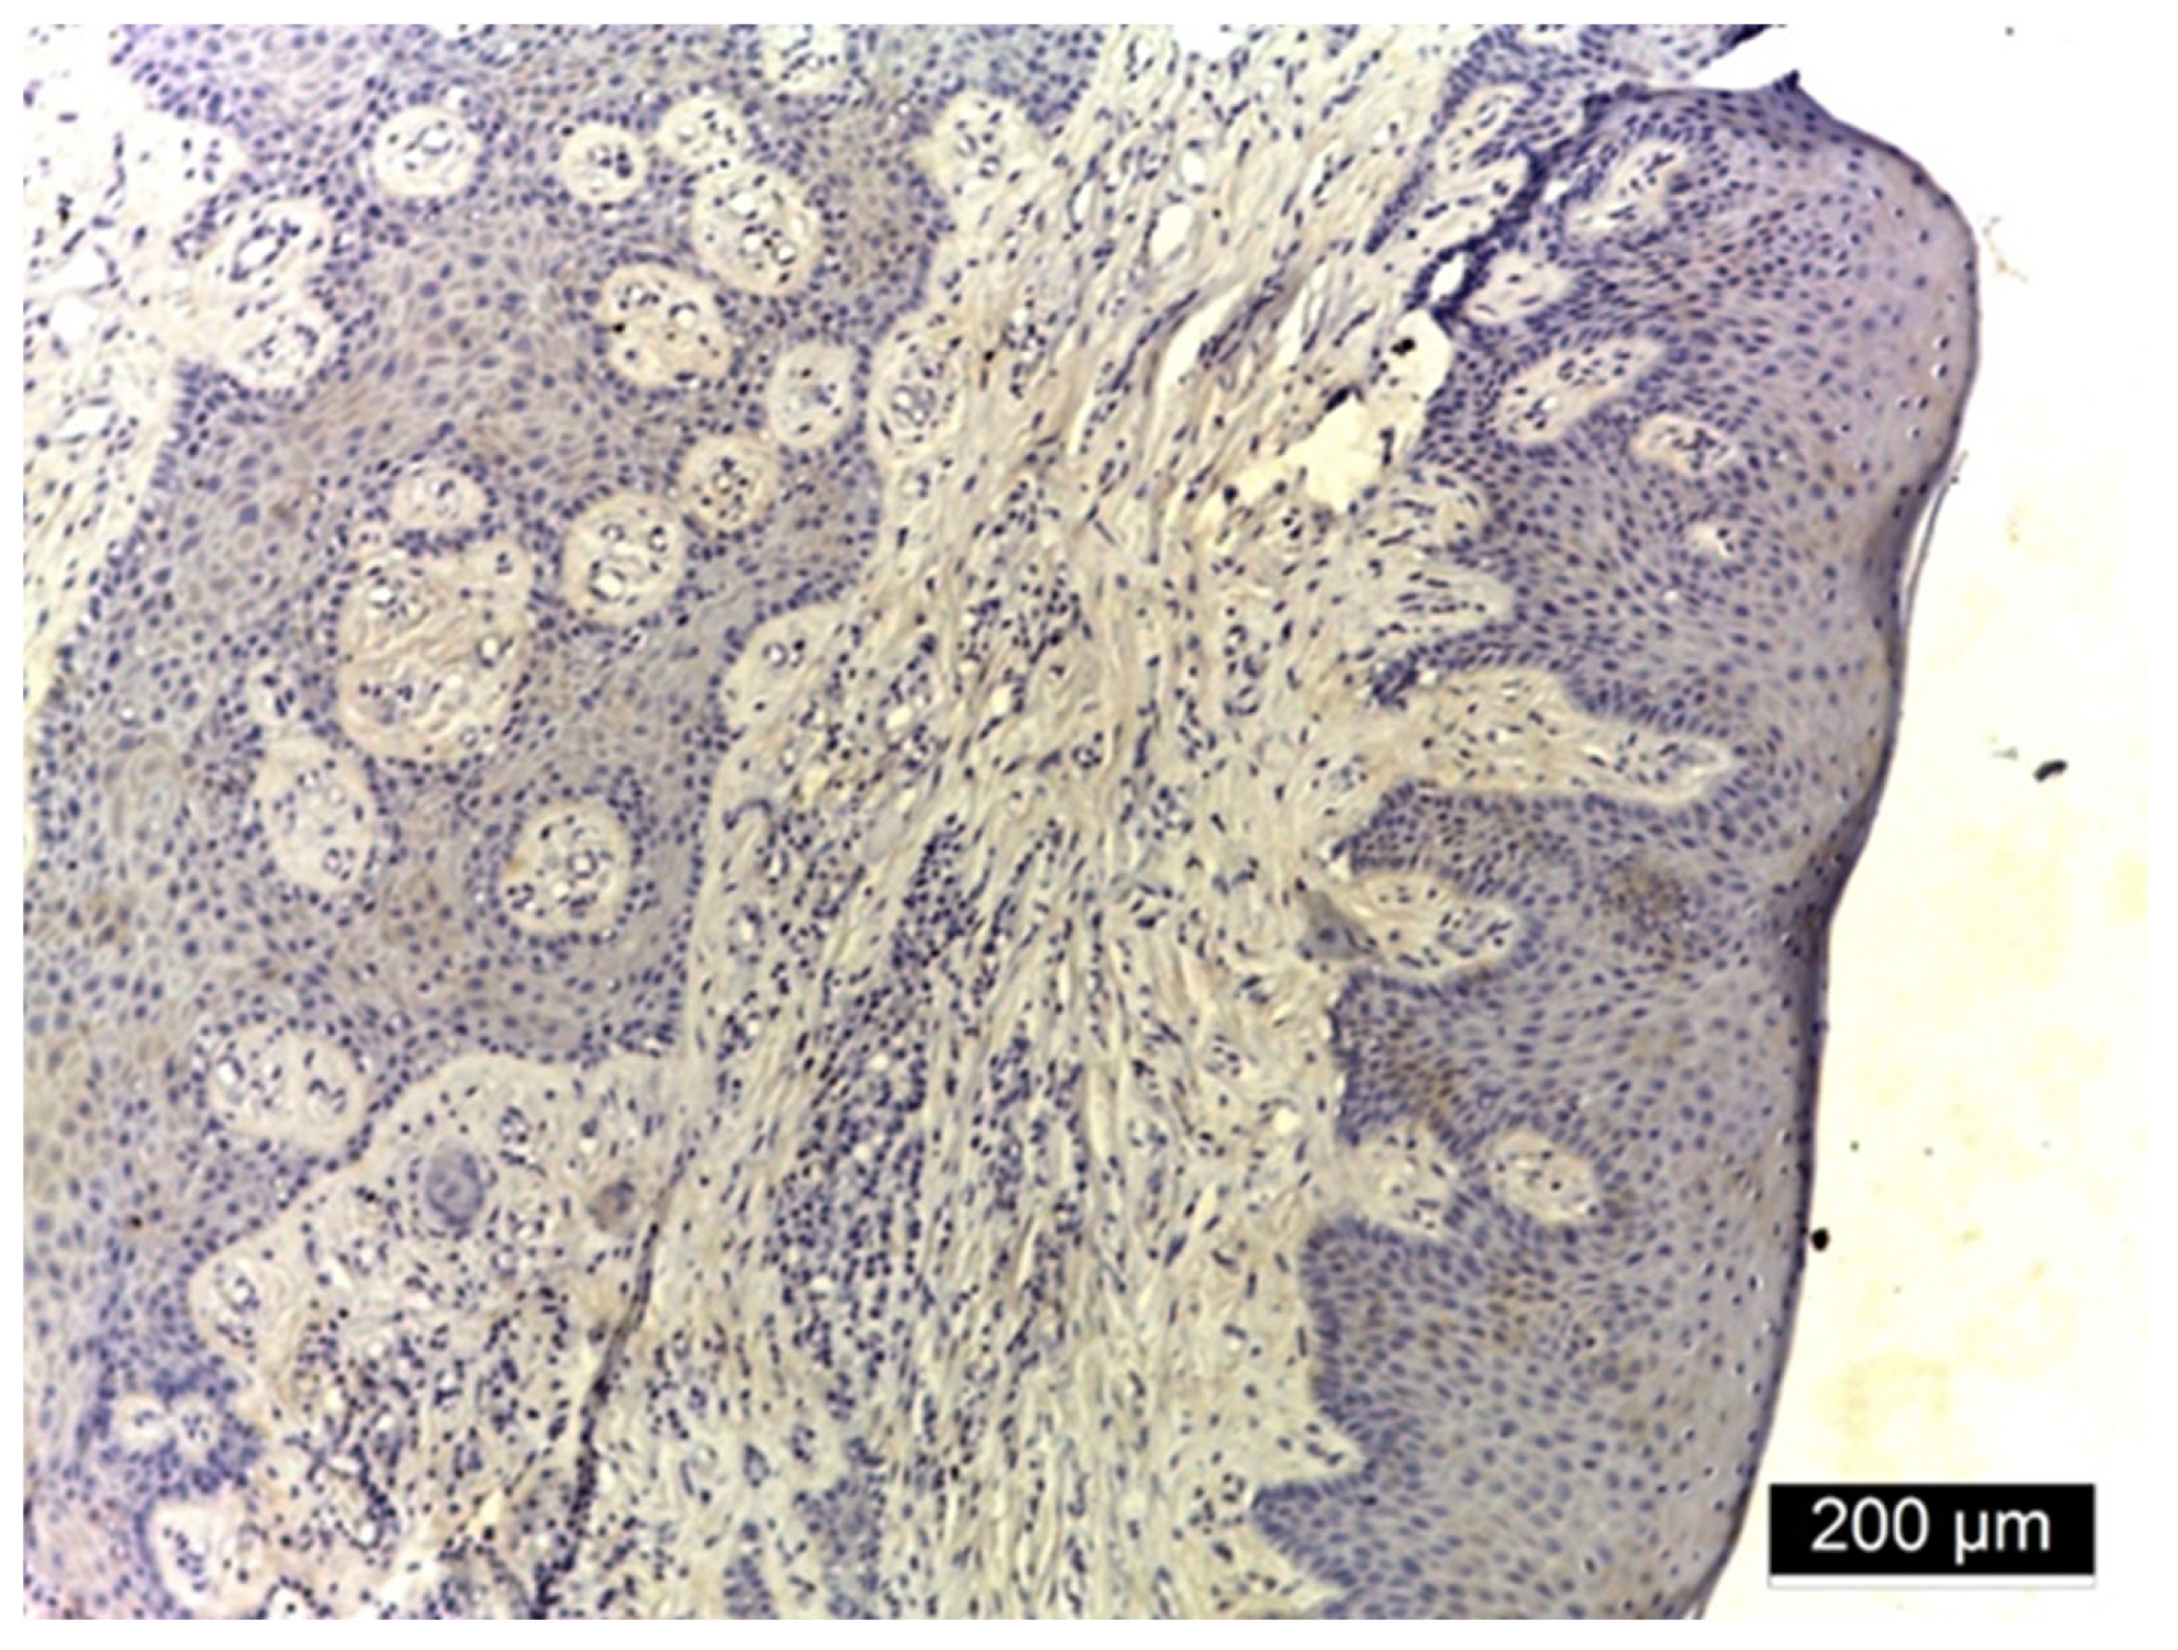

3.2. Ezrin Immunoreactivity

4.1. Ezrin Immunoreactivity